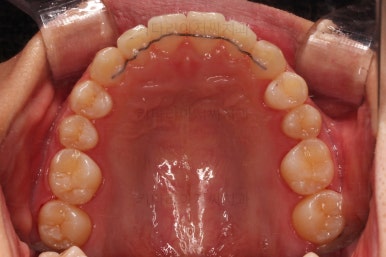

초진 시 입안의 모습이에요.

위아랫니가 모두 삐뚤어요.

특히 앞니가 삐뚤고 위아래 앞니가 고르게 덮여있는게 아니라 뒤죽박죽 엉켜있어서 치아의 마모도 굉장히 많이 되어있는 상태였어요.

치료가 1년만에 종료가 되었네요.

치아가 가지런해졌고, 교합이 잘 맞는 모습이에요.

부산교정 전후사진을 비교해 볼게요.

치열의 모습이 좋아졌고, 웃을 때 보이는 치열이 가지런해서 미소도 훨씬 예뻐졌네요.